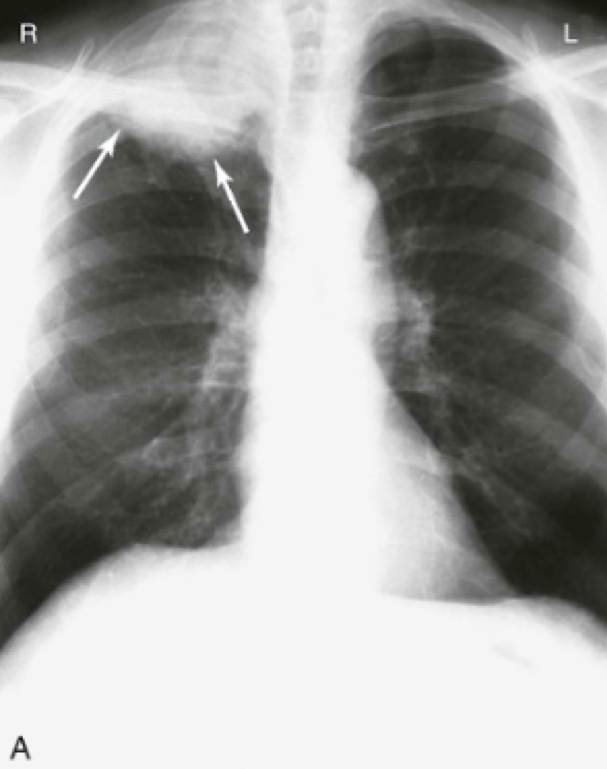

Question 10

Question

What is chronic cavitation is associated with?

Answer

• Mycoplasma

• Kaposi’s Sarcoma

• Pneumocystis jiroveci

• Acute TB